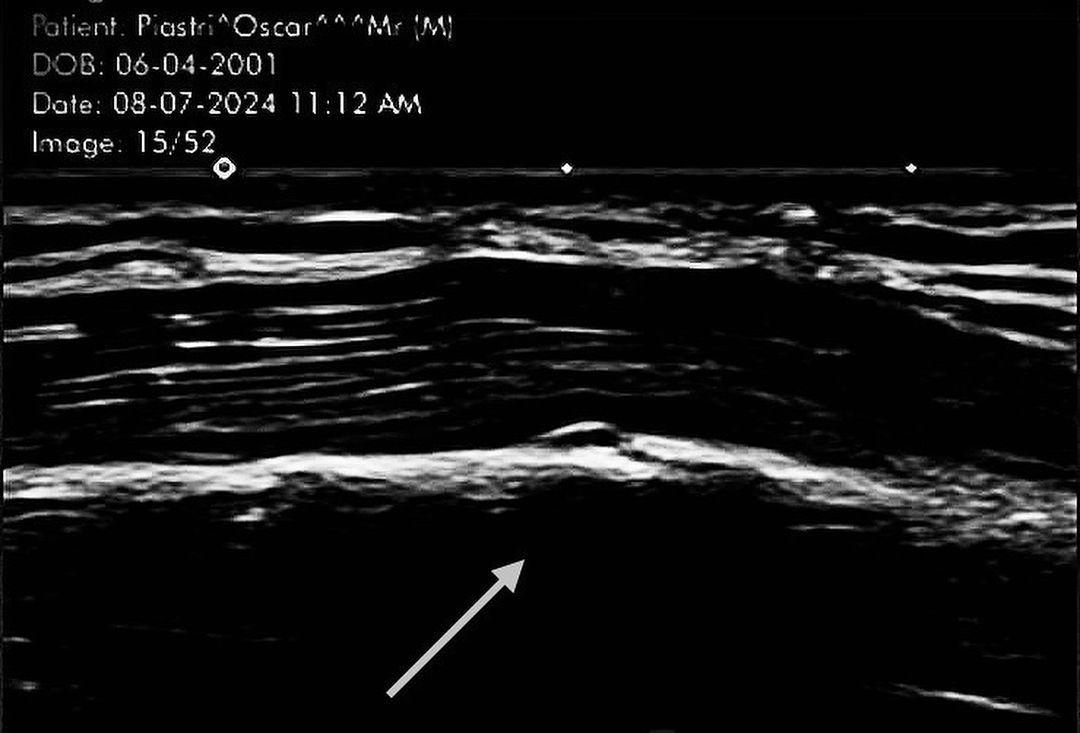

Piastri added no further details, but he did include a picture of what appeared to be an ultrasound scan suggesting that he had suffered a fracture to his sixth rib. It bore the date of July 8, the day after the British GP.

That was just under two weeks before he raced in Hungary suggesting that he would still have been in significant discomfort if not considerable pain as he crossed the finish line at the Hungaroring.